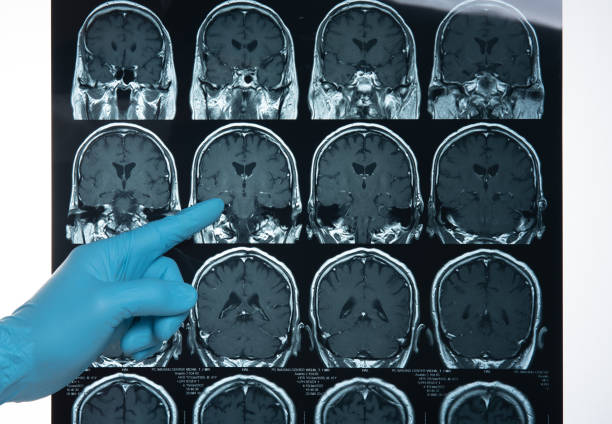

뇌종양을 진단하기 위해 보통 검사 방법은 MRI(자기 공명영상)와 CT(컴퓨터 단층 촬영) 이 있습니다. 검사 방식은 아래와 같습니다.

- MRI(자기공명영상): 뇌의 구조를 자세히 확인할 수 있고 종양의 크기와 위치를 정밀하게 파악하는 데 유용합니다.